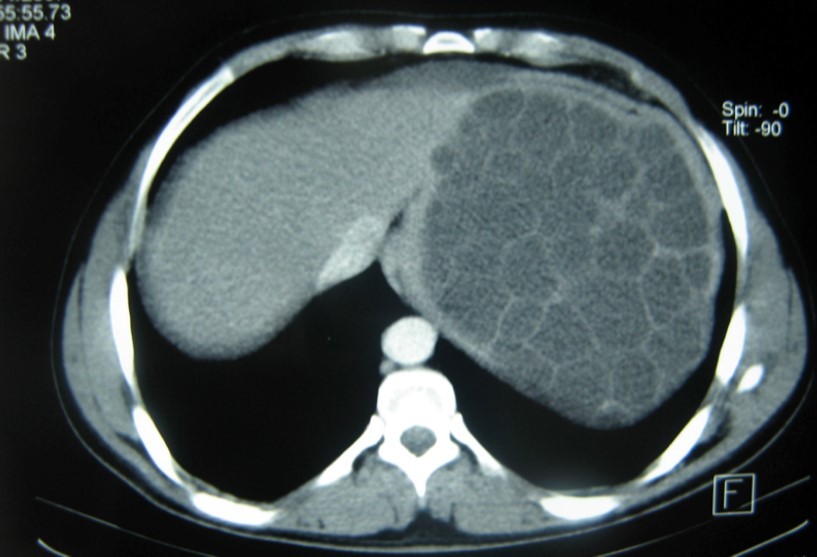

A 17-year-old young man admitted to our department with the complaint of abdominal pain localized in the left upper quadrant for the last 3 months. His physical examination revealed a splenomegaly. Immunoblot assay for Echinococcus was positive. His laboratory tests showed normal results of the serum and urine examinations, No eosinophilia was found. Chest X-ray revealed no pathological signs. An abdominal ultrasonography showed a 20 cm multivesicular cystic mass of spleen (figure 1). Contrast enhanced CT scans detected a huge single 20×16×18cm cystic mass located in the spleen. It had well-defined borders and contained multiple, round, daughter cysts in the periphery of the lesion with calcification (Figure 2, Figure 3, Figure 4). The patient underwent a laparotomy. A large splenic cystic mass was identified, attached to diaphragm, and tail of the pancreas (figure 5). The abdomen was packed with 10% hypertonic saline soaked pads in order to protect peritoneal soilage. A partial cystectomy without splenectomy was performed. Histologic examination of the specimen resection showed an echinococcal organism residing within the hydatid cyst . The patient was discharged after 4 postoperative days. 600 mg per a day of Albendazole therapy was instaured postoperatively and continued for 6 months. Two years after surgery the patient is well with disease free.

Figure 2.CT showing a huge single 20×16×18cm cystic mass located in the spleen

Ct scan is useful for diagnosis and screening, although there are a variety of pathognomonic signs of hydatid disease on imaging, they are not always present. Other cystic lesions of spleen, such as abscess, hematoma, or pseudocyst may be a diagnostic dilemma 5, 12. CT may show the cystic lesion with or without daughter cysts within the spleen with an attenuation value near that of water without any contrast enhancement 10, 11. Hematological examination may reveal eosinophilia. Immunoelectrophoresis, enzyme-linked immunosorbent assay (ELISA), latex agglutination, and indirect haemagglutination test are helpful for the diagnosis 13. A negative serology does not rule out cystic echinococcosis . In these cases the diagnosis can be difficult . Although the sensitivity of serological testing is not clearly dependent on the extent of disease, it does appear to be dependent on cyst stage. 14. echinococcal IgG ELISA test has perhaps the highest positive predictive value among the available serological tests, but unfortunately may only have a negative predictive value of <90% 14. A rapid immunochromatography test kit using the recombinant Em18 antigen was recently developed. It seems be simple, reliable, and easy-to-use 15.